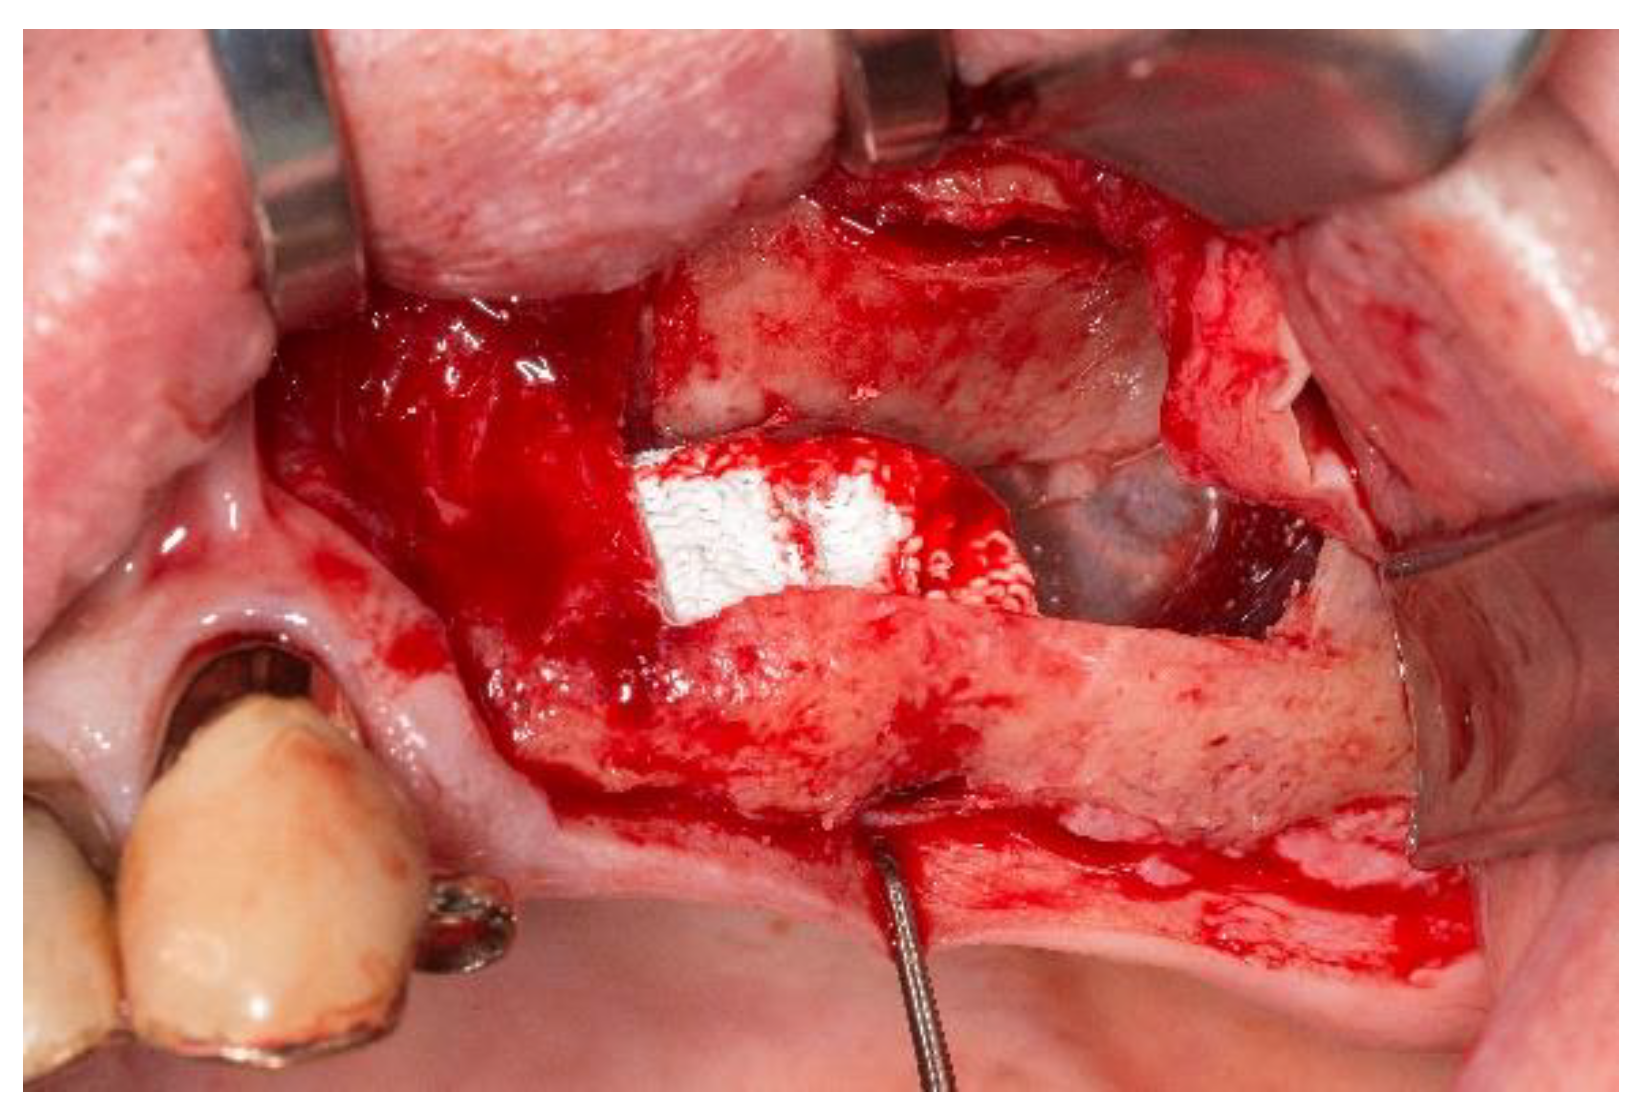

Next, the bilateral sinus floor elevation was performed using the calcium-phosphate scaffolds. All surgeries were performed according to the department’s standard in local anesthesia using Ultracain DS (Sanofi Aventis Deutschland, Frankfurt, Germany). Following a crestal incision with a mesial relief incision, a mucoperiosteal flap was elevated. The access cavities were prepared using a piezosurgery device (Piezosurgery® 3, mectron Deutschland Vertrieb, Köln, Germany). The resulting bone lid was deflected cranially and remained pedicled on the Schneiderian membrane (Figure 3). On the left side, a small rupture of the Schneiderian membrane occurred which was sutured with absorbable material (Vicryl 5-0, Johnson & Johnson Medical GmbH, Ethicon Deutschland, Norderstedt, Germany). Subsequently, the calcium-phosphate scaffolds were placed in the sub-antral space and fixed with each one micro screw (1.5 × 7 mm; Gebrüder Martin, Tuttlingen, Germany). The scaffold in the right maxilla was measuring approximately 10 × 10 × 8 mm and in the left maxilla 10 × 14 × 8.5 mm, respectively. After the repositioning of the mucoperiosteal flap, the wound closure was performed using non-absorbable sutures (Prolene monofil 5-0, Johnson & Johnson Medical GmbH, Ethicon Deutschland, Norderstedt, Germany). Ibuprofen was administered as analgesic. The postoperative behavioral instructions contained the application of cool packs, a liquid diet and the use of decongestant nasal spray. In order to examine the correct position of the scaffolds, a postoperative CBCT was performed.

Figure 3.

The intra-operative situs after fixation of the scaffold in the left maxillary sinus with a fixation screw on the crestal bone. The access bone lid is deflected into the maxillary sinus.